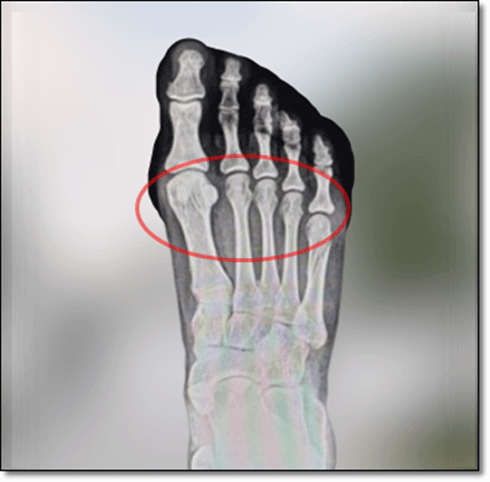

중족골은 발가락의 지골과 족근골 사이에 있는 중간 뼈로, 발끝 쪽과 바닥에 지방층이 있는데 여기에 염증이 생겨서 통증이 생기는 것을 중족골 통이라고 합니다. 중족골 통은 아침에 첫발을 디딜 때 발 뒤꿈치 쪽이 아픈 족저근막염과 달리 발바닥 앞쪽에 통증이 발생하며, 오랫동안 앉았다 일어날 때 통증이 느껴지기도 합니다. 또한 격렬한 운동과 맞지 않는 신발, 체중 등으로 발등뼈에 부적절한 부하를 받았을 때 생기는 통증이 중족골 통입니다.

중족골통은 발등뼈인 중족골에 압력이 가해지면서 통증을 일으키는 것으로, 흔히 두 번째 중족 골도에 생기는 경우가 많습니다. 특히 보통 사람보다 두 번째 발등뼈가 긴 사람은 압력을 많이 받아서 생기기도 하지만, 발등뼈가 짧은 경우에도 굽이 높은 신발을 신을 때에 쉽게 발생할 수 있습니다. 또한, 무지외반증으로 인해 엄지발가락이 옆으로 휘면서 두 번째 중족골두에 하중을 많이 받으면서 통증이 생길 수도 있습니다.

중족골은 발목뼈와 발가락을 연결하는 다섯 개의 긴 뼈를 말하는 것으로 발바닥의 아치와 발가락 사이에 위치합니다. 또한, 중족골통은 발가락의 기저부인 중족골에서 통증을 유발하는 염증이 생겨서 자주 달리거나 점프하는 사람, 앞부분이 좁은 신발을 신는 사람, 발이 변형된 사람에게 흔하게 발생합니다. 중족골통은 심각한 질환은 아니지만 걸을 때 발생하는 통증 때문에 일상생활에 많은 불편함을 주기도 합니다.